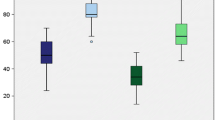

Varus laxity

A 5Nm varus moment resulted in an average tibial varus rotation of approximately 4° in an intact knee from 10° to 100° flexion (Fig. 7). Isolated PCL resection did not increase the varus laxity measurably. Cutting the PCL and the PLC resulted in a significant increase in the varus laxity from 10° to 100° (P < 0.001). Both the modified Larson as well as the anatomic reconstruction restored the knee to the isolated PCL deficient condition (P > 0.05) and, hence, also restored the knee to the intact knee condition, from 0° to 100° flexion. A significant difference was not found between the reconstructions at any angle of knee flexion (P > 0.05). Both the reconstructions were significantly different from the combined PCL and PLC-deficient knee throughout the arc of knee motion except at 0° (P > 0.05 at 0°; P < 0.001 at 20°–100° flexion).